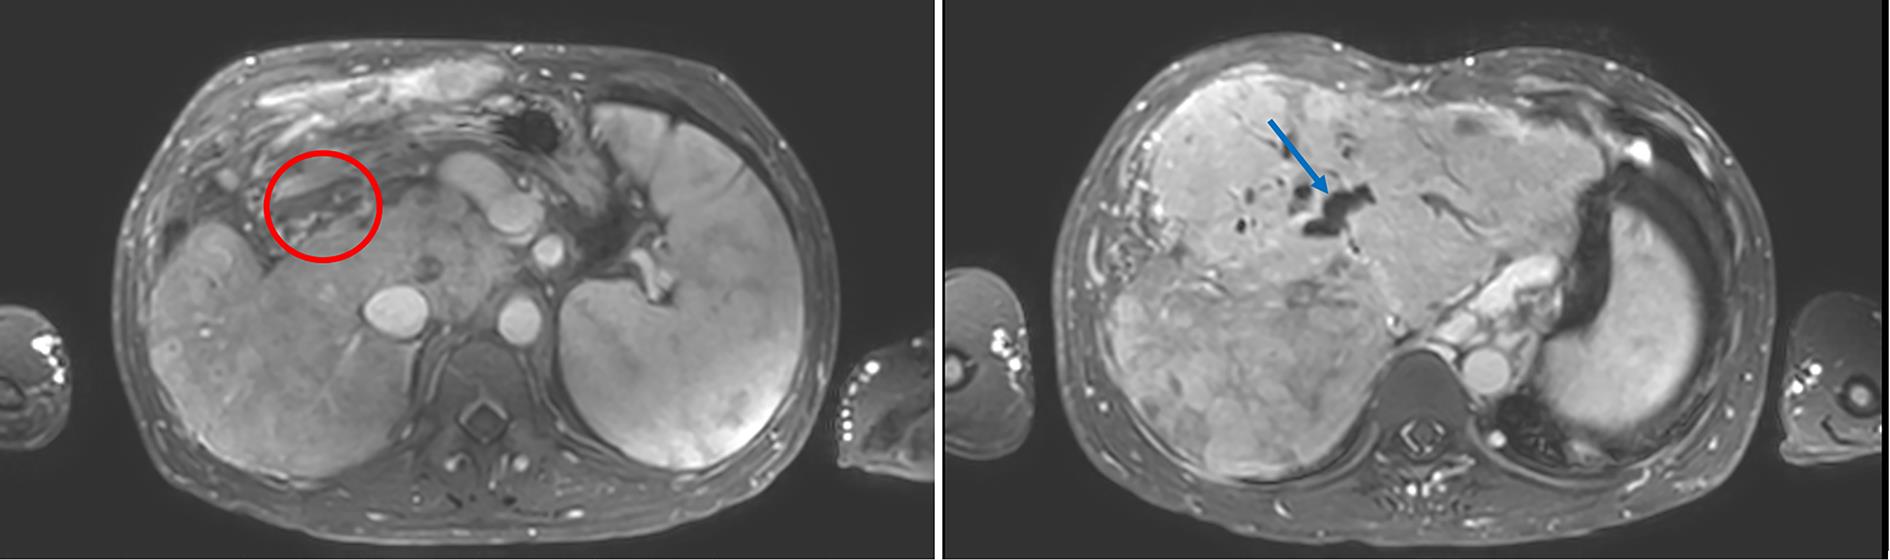

Transcatheter closure of rare type Ⅱ Abernethy malformation with pulmonary hypertension in children: A case report

Heng ZHANG, Bin JIANG, Zhicheng FANG, Zhongji MENG, Enfu DU

2023, 39(11): 2663-2667. DOI: 10.3969/j.issn.1001-5256.2023.11.022

Abstract(978) HTML (281) PDF (1074KB)(76)

Abstract:

Abernethy malformation, also known as congenital portosystemic shunts, is rare in clinical practice, with less than 300 cases reported in the global literature up to 2019. The disease can have serious complications such as pulmonary hypertension, liver tumor, and liver failure and tends to have an extremely poor prognosis, and early diagnosis and active and effective treatment can reduce and delay the onset of complications. In this case, portography combined with balloon occlusion helped to display the underdeveloped slender portal vein with dysplasia, so that the child who was formerly misdiagnosed with type Ⅰ Abernethy malformation was diagnosed with type Ⅱ Abernethy malformation, and then the child was successfully treated by transcatheter closure. This article gives a detailed report of this case.